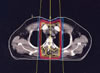

Thymuskarzinom